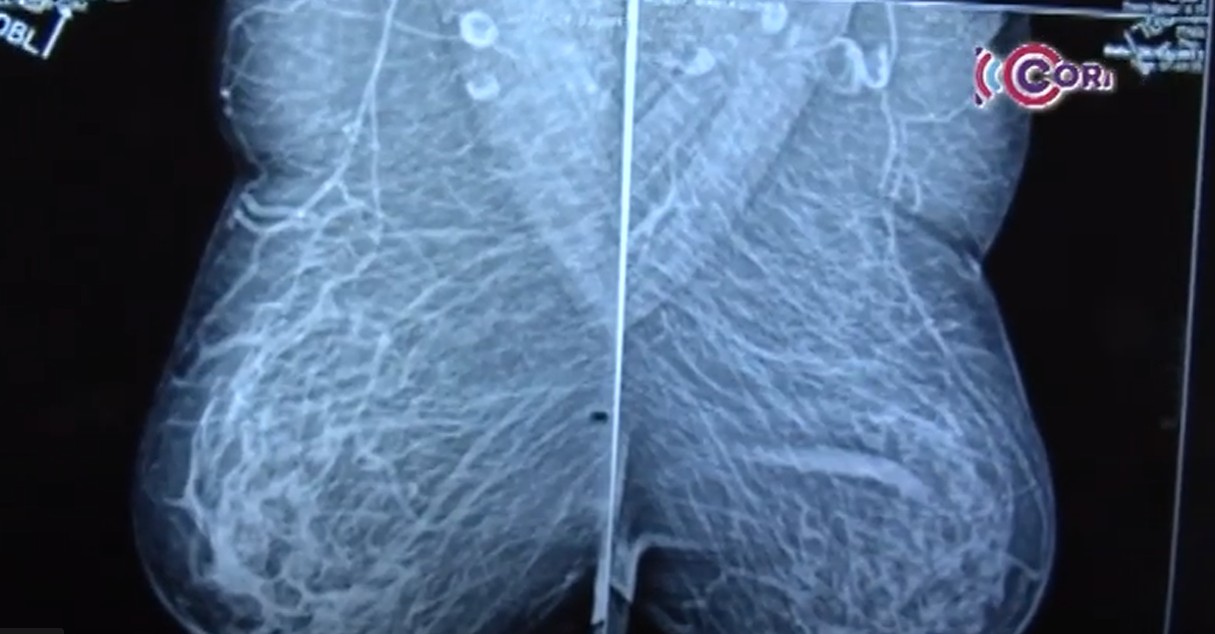

Intensifica SESA la campaña de prevención del cáncer masculino

En lo que va del año se han registrado 10 casos de cáncer en hombres en Tlaxcala, principalmente de colon,...